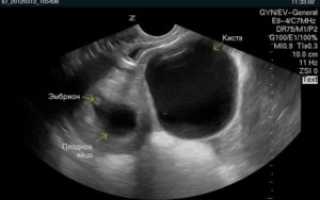

Киста желтого тела или лютеиновая киста – это доброкачественное новообразование на яичниках женщины. Внешний вид напоминает гладкую толстостенную капсулу, образованную из яичниковой ткани и заполненную желтой жидкостью.

Такая разновидность патологии может размещаться как на правом, так и на левом яичнике и в размерах достигать до 8 см. По строению киста может быть однополостной и многополостной.

При благополучном оплодотворении, желтое тело продолжает свою функциональную обязанность и синтезирует прогестерон еще на протяжении 12 недель, тем самым, выполняя роль плаценты. По прошествии данного срока производство гормона ложится на плацентарную оболочку, а желтое тело самопроизвольно рассасывается (иногда желтое тело продолжает свою жизнедеятельность в виде кисты).

На ранних сроках беременности чаще всего может возникнуть киста желтого тела (лютеиновая).

Этот вид новообразования развивается из желтого тела, которое необходимо для правильного формирования плаценты. Если будущей мамочке был поставлен данный диагноз, волноваться не стоит.

Лютеиновая киста не угрожает беременности, не увеличивается в размерах и после 12 недель самостоятельно рассасывается.

- лютеиновая или киста желтого тела. Она появляется чаще остальных разновидностей, зачастую на раннем сроке беременности. В кистозный мешок преобразовывается желтое тело, такое новообразование рассасывается само, когда функцию выработки прогестерона на себя перенимает окончательно сформировавшаяся плацента. Подобные опухоли имеют небольшие размеры, поэтому они безопасны как для матери, так и для плода;

Не исключено одновременное развитие беременности и кисты желтого тела в течение 4 недель после зачатия. Опухоль не имеет противопоказаний к вынашиванию ребёнка, и способствует стабилизации гормонального фона.

Также киста яичника у плода не вызывает нарушений в развитии. В 95% случаев опухоли этого типа рассасываются во втором триместре, ближе к 9 неделям. Иногда гинеколог не может определить, что у женщины: киста желтого тела или беременность.